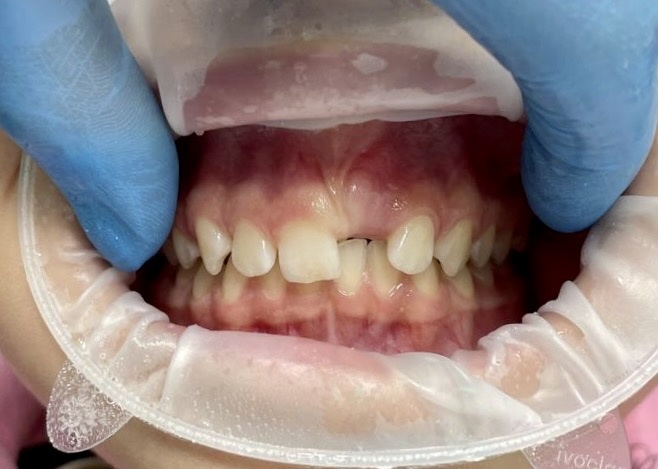

Следующий приём ещё через 1.5 месяца, снова контрольные фотографии:

Что дальше?

В ближайшее время установка брекет-системы на нижнюю челюсть и 1 - 1.2 года коррекции.

Что с десной в области зуба 2.1?

Варианты:

1. оставить так - не лучший выбор. Уздечка верхней губы вплетена в межзубный сосочек и может в дальнейшем создавать напряжение, стремясь резцы разобщить;

2. пластика десны - верное решение.Будет выполнена пластическая операция, направленная на перемещение уздечки и уменьшение рецессии (или увеличение коронковых частей остальных зубов). Время покажет, какой вариант предпочтительнее. Вопрос на 100% решаемый.